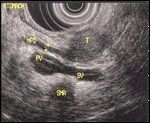

Neuroendocrine Pancreatic Tumor-main pancreatic duct (MPD), tumor (T), portal vein (PV), splenic vein (SV), superior mesenteric artery (SMA)